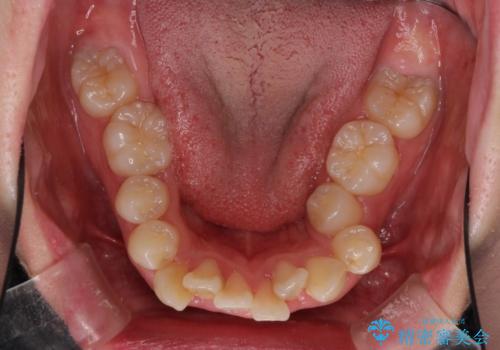

著しい叢生と顎骨のズレ ワイヤー装置による抜歯矯正

- 前歯の著しい叢生や八重歯を気にして来院された患者様です。

上下の顎がずれており、上下の正中は歯1本分の差がありました。

上下左右の小臼歯4本を抜歯し、極力正中を合わせるように矯正治療を始めていくこととしました。

咬み合わせの乱れが著しく、治療途中で一部反対咬合となってしまいました。

アンカーなどをうまく使用して、3年の期間を要してきれいに仕上げることができました。